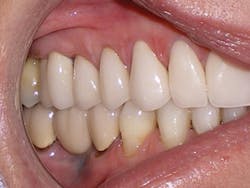

Dr. Miraglia: Victoria's long-term history and recovery

Figure 4

Victoria validated this by describing that she had been going to the dentist routinely, always needing something repaired. In Victoria's case, as with many others, the cause was the malocclusion; the indicated treatment was to develop the arch form and width, and to level and align the teeth to deliver a better, protective occlusion.

After taking a full set of records, Victoria's consultation involved using her photographs to teach the extent of the deterioration her malocclusion had caused. We discussed recession, bone loss, periodontal probing depths, abfractions, gingivitis, decay, fractured cusps, worn enamel, failed restorations, and continued deterioration. We taught the difference between a good bite and a bad bite and discussed the opportunities to treat the cause of the deterioration with clear aligners first and then perform the restorative dentistry second.

Victoria agreed to our recommendation. Clear aligner therapy was accomplished with 25 aligners, which took 12 months. Then, full-coverage esthetic restorations were placed on teeth Nos. 3-14 and also teeth Nos. 19 and 20. A lower lingual bar was bonded to all six lower anterior teeth, Nos. 22-27.

Correcting the malocclusion directly contributed to the improvement in the health of the gum tissue. The restorative dentistry was accomplished easily thanks to the gum tissue being pink, healthy, and tight, with shallow pockets. After completing the comprehensive care treatment for Victoria, she was placed on a four-month recall that she continues to maintain. Five uneventful years have passed, and the five-year follow-up photos show stability and health. Victoria enjoys all of the function and strength from her good bite and dental restorations without any deterioration at the five-year mark. The key to periodontal health and restorative success and stability is the correction of the malocclusion. The clear aligner therapy was the cornerstone of this comprehensive treatment plan.